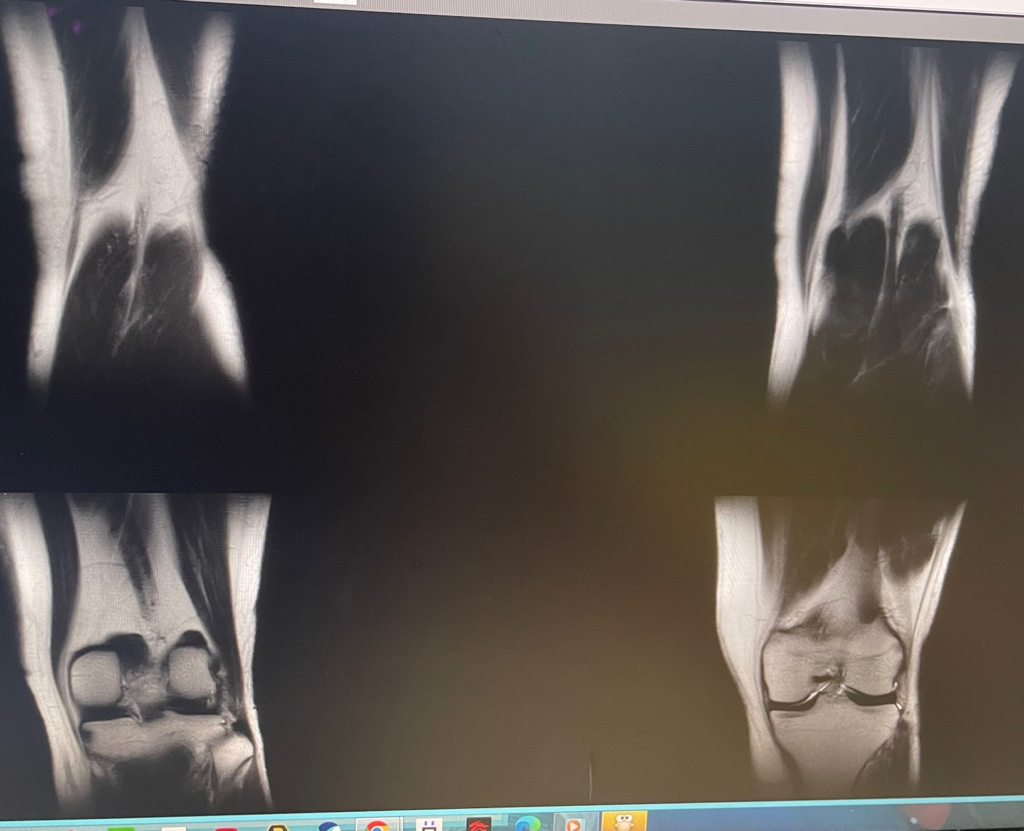

무릎 mri 원형원골인지 봐주실 수 있을까요

무릎이 너무 자주 아파서 mri를 찍어봤는데 무릎 연골에 이상이 있을까요

무릎이 선천적으로 원형연골인지 봐주시면 감사하겠습니다

MRI 판독에는 퇴행성 연골 손상, 바깥쪽 원판형 반월상 연골 이 의심된다고 적혀 있습니다.